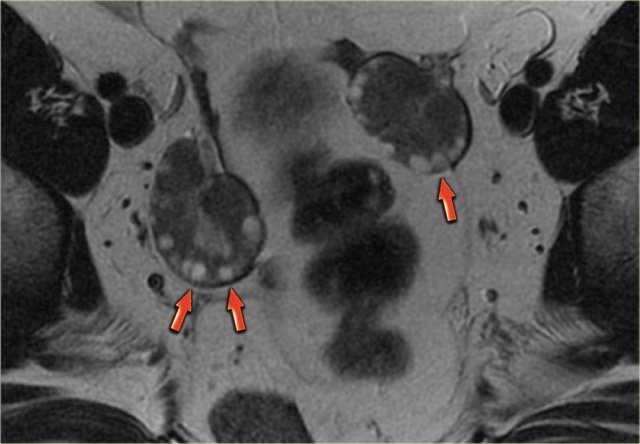

CT of the same patient shows a complex solid-cystic mass with thick, enhancing septations in the right ovary.

These findings are very suspicious for a malignant cystic neoplams.

There is also bilateral lymphadenopathy (arrows).

Pathology showed a serous ovarian cystadenocarcinoma.